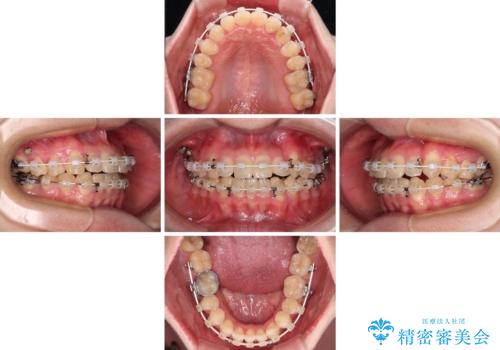

【モニター】1本欠損した下顎前歯と上顎の八重歯 ワイヤー装置で楽して矯正治療

- 八重歯を気にして来院された患者様です。

診査を行ったところ、下顎前歯が1本欠損しており、下顎歯列が上顎よりも小さくなっていることで、上顎にデコボコが生じていました。

口元を見ると抜歯をして突出感を改善するような状態ではなかったため、上顎歯列のデコボコを整えて、歯列全体を後方に移動させることでバランスを取ることとしました。

マウスピース矯正は自己管理が煩わしいとのことで、ワイヤー装置にて矯正治療を行うこととしました。